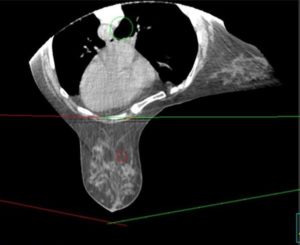

We treat the patient in a prone position, causing the breast to fall away from the chest. This enables us to direct the beam of radiation to the breast but not the chest, reducing radiation exposure to the heart and lungs.